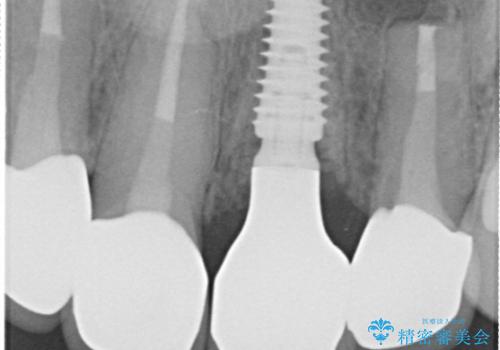

- 治療計画

- 患者様は前歯の審美的な改善を希望されて来院されました。診査の結果、左上1の歯は過去の根管治療により歯根が破折していることが判明し、保存が難しい状態でした。そのため、**長期的な予後を考慮し、抜歯と同時にインプラントを埋入する「抜歯即時インプラント」**を計画。また、隣接する左上2の歯には感染が見られたため、歯根端切除術を同時に行い、感染の除去と治癒を促しました。右上1・2については、セラミッククラウンによる審美修復を行う方針としました。

左上1は抜歯と同時にインプラントを埋入し、骨や歯ぐきの形態を維持しながら治療を進めました。左上2は歯根端切除術により感染部位を除去し、保存治療を実施。右上1・2も含めた前歯4本をセラミッククラウンで修復し、自然な色調と形態を再現しました。治療後は、噛み合わせの安定とともに、美しく自然な前歯を回復することができました。患者様からも「見た目がとても自然で、自信を持って笑えるようになった」と喜びの声をいただきました。